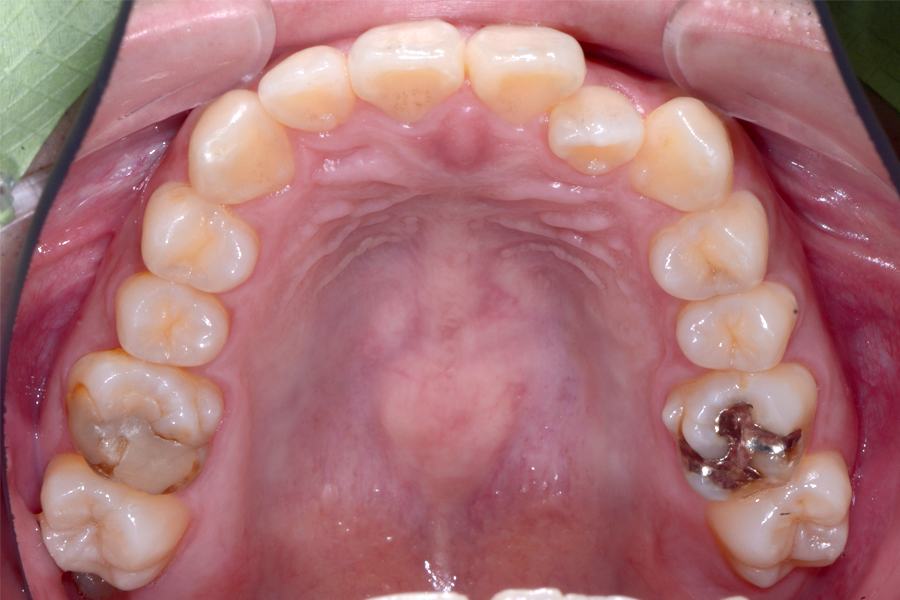

• 治療前

治療後

主訴 上下の捻じれている歯を綺麗にしたい

治療内容 上下顎ラビアル矯正(表側矯正)

リスク 後戻り